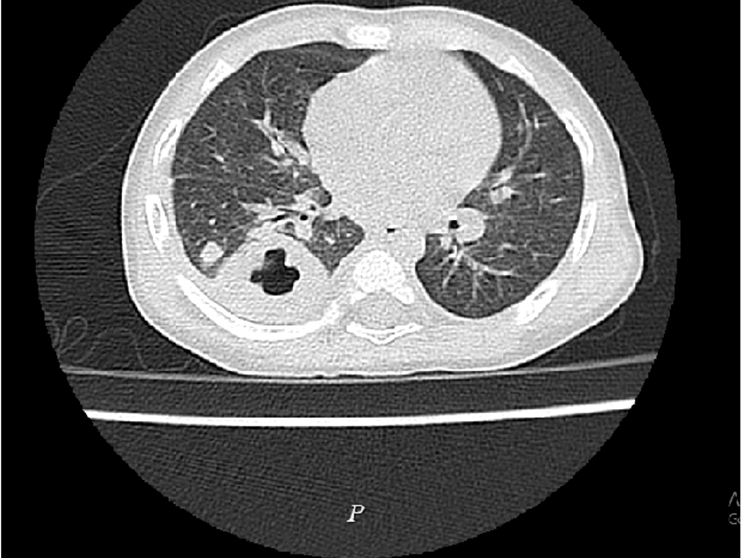

Các bác sĩ Khoa Nhi, Bệnh viện Đa khoa Hùng Vương, ngày 19/8 cho biết kết quả xét nghiệm máu, chụp X-quang tim phổi, cấy máu, chụp cắt lớp vi tính phổi, cho thấy bé bị nhiễm khuẩn huyết, áp xe phổi. Ba ngày sau, kết quả cấy máu cho thấy bé dương tính với Whitmore (Burkholderia pseudomallei).

Bệnh viện Đa khoa Hùng Vương hội chẩn với các bác sĩ Bệnh viện Nhi Trung ương, dùng kháng sinh điều trị, phẫu thuật dẫn lưu mủ trong phổi. Sau đó bé được chuyển về Bệnh viện Nhi Trung ương, Hà Nội, điều trị tiếp.